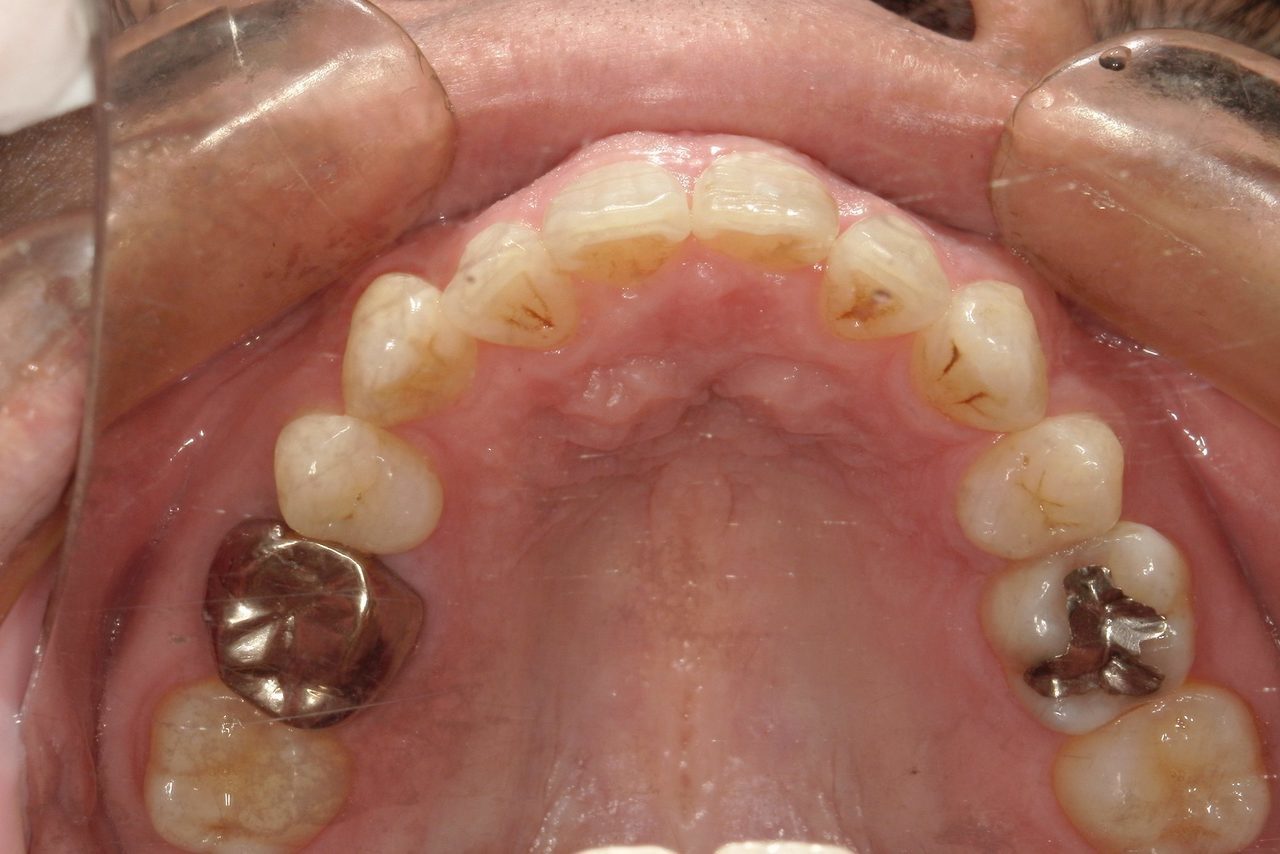

Before

浜松市中央区・自動車学校前駅のインビザラインの症例

Y.S. 30代男性

全体的にガタガタしているのが気になるという主訴だったため、上下左右第一小臼歯を抜歯し、叢生を並べました。

治療の期間:R3. 9/1〜R5. 10/31

治療の価格:88万円